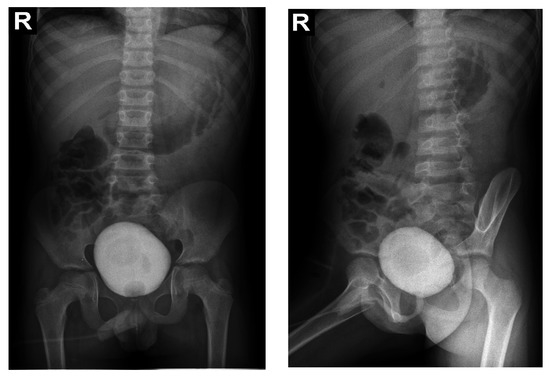

Voiding mictional cystourethrogram (Figure 1)

excluded the presence of a posterior urethral valve or primary vesicoureteral reflux

Figure 1. Voiding mictional cystourethrogram.

Due to the poor medical condition, with advanced renal failure, acidosis, arterial hypertension, the patient required the urgent initiation of hemodialysis. At the same time, we continued investigations for the etiology of renal failure (Table 1). We excluded the reflux nephropathy (secondary to primary or secondary vesicoureteral reflux, or posterior urethral valve) by voiding cystourethrogram (Figure 1).